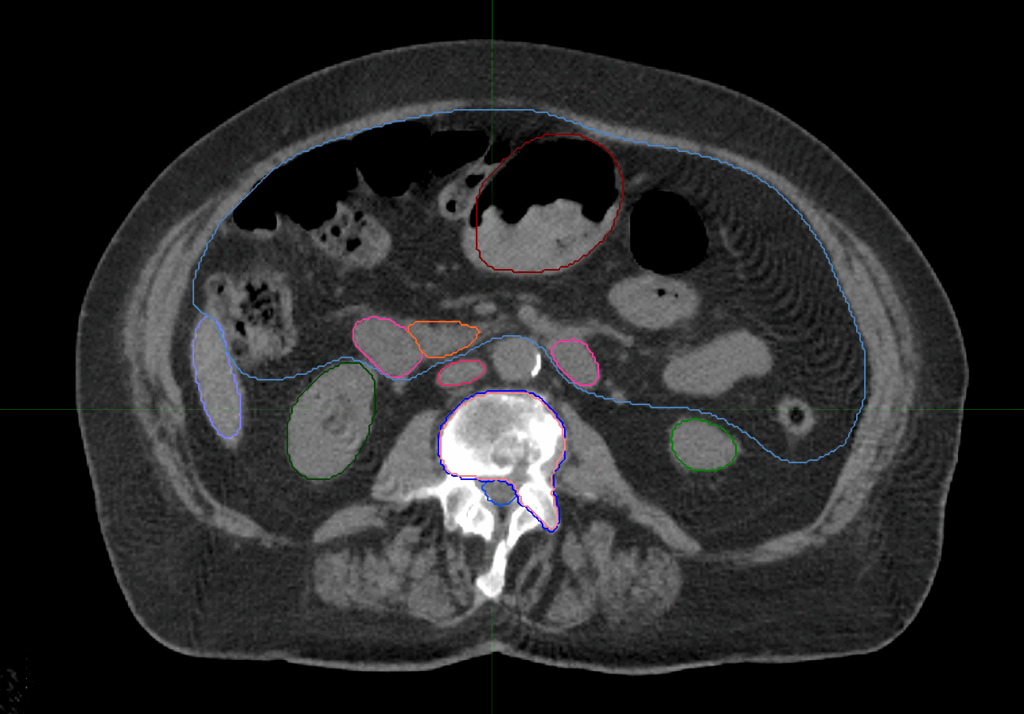

Planning CT Images

Treatment Plan Images

Treatment Planning Highlights

Fractionation

27 Gy in 3 fractions

PTV(s) Volume

PTV, 62.5 cc

Dose Distributions

- Prescription to the

74.5% isodose line - Max. dose 36.24 Gy

Collimator

Iris Variable

Aperture Collimator

Dose Calculation Algorithm

Monte Carlo

New Conformality Index (nCI)

nCi = 1.15

Protocol Used

SABR UK Consortium